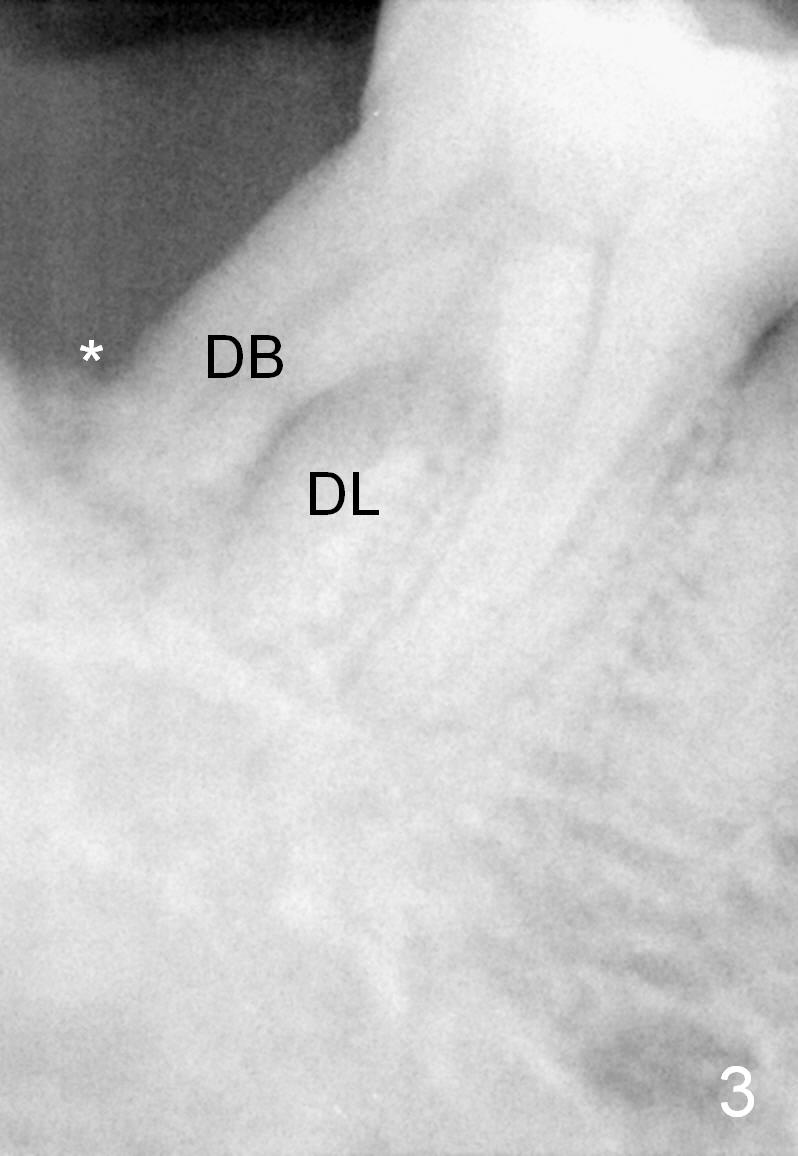

One year and a half years ago, the tooth #31 of a 48-year-old man had infection (Fig.1 *) and was extracted without implant. There was more bone loss in the distal of #30 than in the mesial (Fig.2 *). Recently the patient returns with infection at #30 distally with severe bone loss (Fig.3 *). An immediate implant is to be placed mainly in the mesial socket (Fig.4 (bone-level), Fig.5 (tissue-level)).